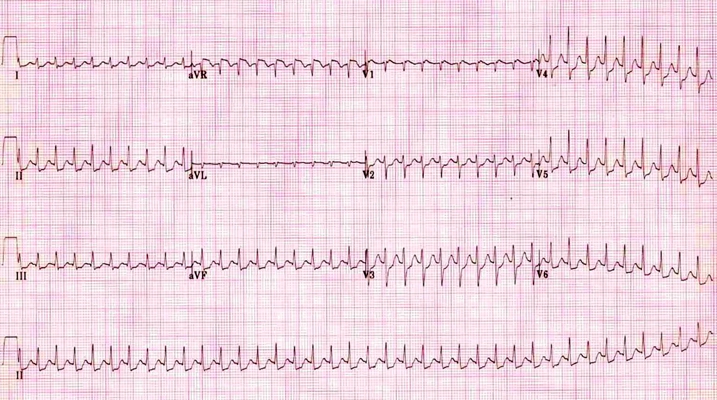

預激綜合徵心電圖 (9)

預激綜合徵心電圖 (90)

預激綜合徵心電圖 (91)

預激綜合徵心電圖 (92)

預激綜合徵心電圖 (93)

預激綜合徵心電圖 (94)

預激綜合徵心電圖 (95)

預激綜合徵心電圖 (96)